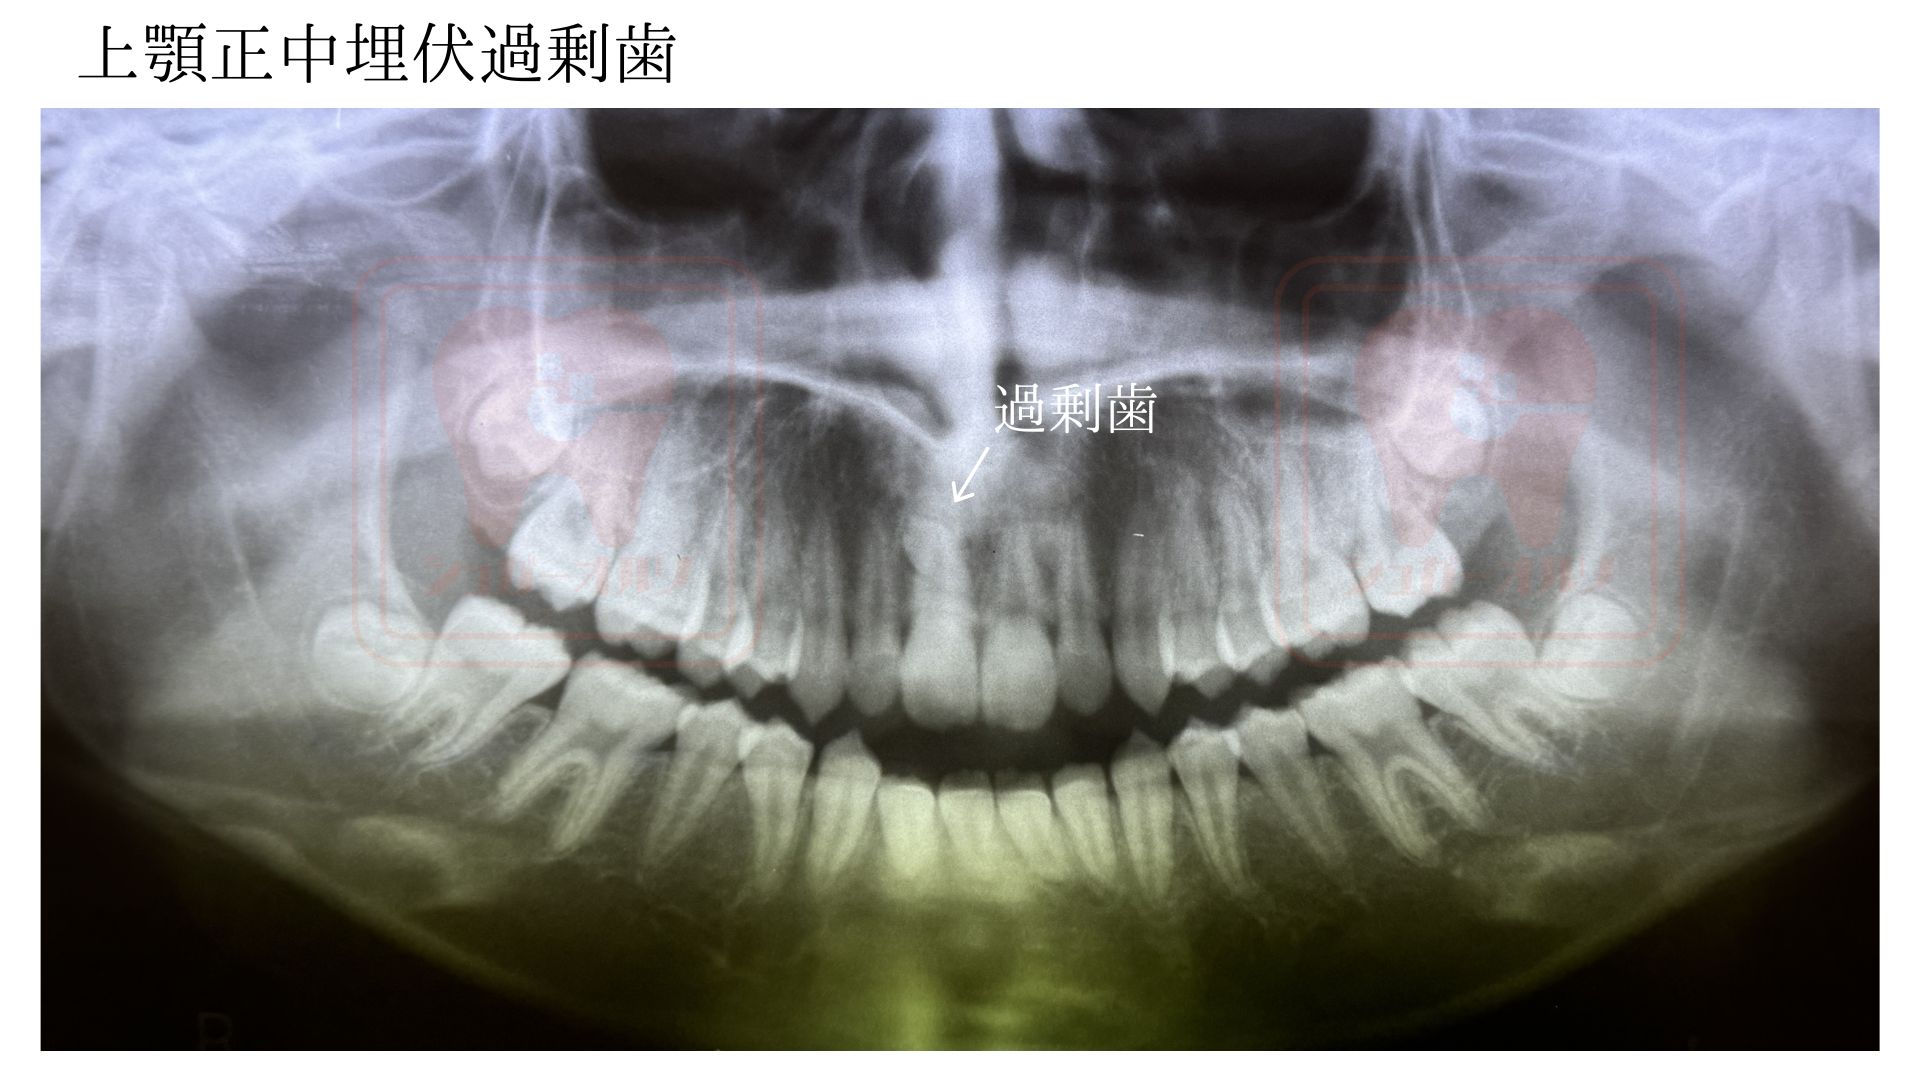

インビザライン 過剰歯抜歯症例

16歳 女性 |

| 診断 | 叢生、反対咬合 |

| 治療方針 | 上顎正中埋伏過剰歯抜歯して、矯正治療を行う。 |